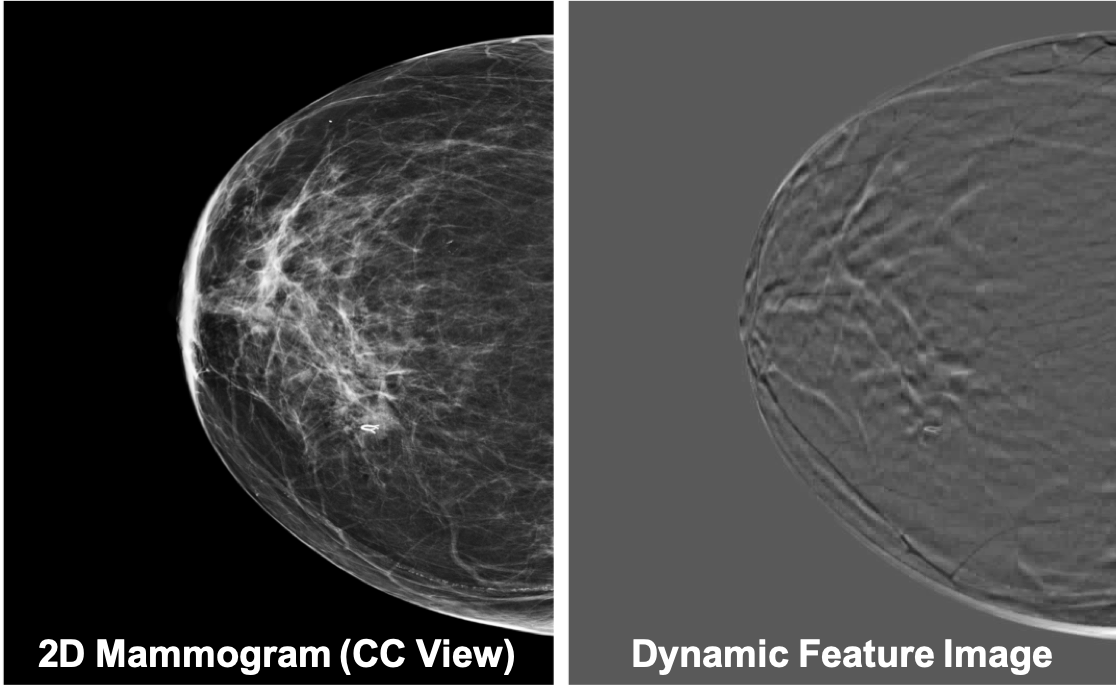

In non-medical domain, a popular method to represent a series of images is to apply a temporal pooling operator to the features extracted at individual images, for instance, temporal templates [21], ranking functions [22] and sub-videos [23], as well as other traditional pooling operators [24]. We adopt the idea of temporal pooling operator to the medical imaging domain. Inspired by Bilen et al., we applied RankSVM [25] directly on DBT data to extract a fixed, one-slice representation of each DBT. Since the extracted fixed representation keeps the dynamic features (i.e., the slice-to-slice changes) of DBT, we call it dynamic feature image. See Figure 2 for an example.

Figure 2: Example of DM and the corresponding dynamic feature images.

One dynamic feature image is a single RGB image, which captures the slice-to-slice changes of a DBT. A ranking function is used to obtain the dynamic feature image for a series of slices I1subscript𝐼1I_{1},…,ITsubscript𝐼𝑇I_{T}, temporally. More specifically, let ψ(It)d𝜓subscript𝐼𝑡superscript𝑑\psi(I_{t})\in\mathbb{R}^{d} be the feature vector extracted from each individual slices Itsubscript𝐼𝑡I_{t} in the series. Let Vt=1tτ=1tψ(Iτ)subscript𝑉𝑡1𝑡superscriptsubscript𝜏1𝑡𝜓subscript𝐼𝜏V_{t}=\frac{1}{t}\sum_{\tau=1}^{t}\psi(I_{\tau}) be the average time of these features up to time t𝑡t. The ranking function associates to each time t𝑡t a score S(t|𝒅)=𝒅,Vt𝑆conditional𝑡𝒅𝒅subscript𝑉𝑡S(t|\bm{d})=\langle\bm{d},V_{t}\rangle, where 𝒅d𝒅superscript𝑑\bm{d}\in\mathbb{R}^{d} is a vector of parameters. The function parameters 𝒅𝒅\bm{d} are learned so that the scores reflect the rank of the slices in the series. Therefore, later times are associated with larger scores, i.e. qtS(q|𝒅)>S(t|𝒅)succeeds𝑞𝑡𝑆conditional𝑞𝒅𝑆conditional𝑡𝒅q\succ t\Rightarrow S(q|\bm{d})>S(t|\bm{d}). Learning 𝒅𝒅\bm{d} is posed as a convex optimization problem using the RankSVM function: